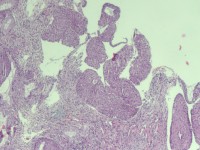

性别

女

年龄

38岁

临床诊断

宫颈病变

一般病史

宫颈癌筛查:HPV52(+)

标本名称

宫颈6点组织

大体所见

灰白色组织1块

可以诊断CIN几级

图3

HSIL(CIN3)累腺